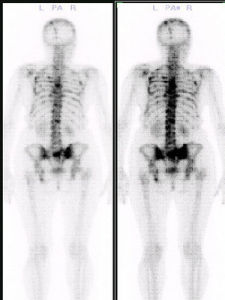

骨掃描是一種全身性骨骼的核醫學影象檢查,它與局部骨骼的X線影象檢查不同之處是檢查前先要注射放射性藥物,等骨骼充分吸收,一般需2~3小時後再用接受放射性的 儀器(如γ照相機、ECT)探測全身骨骼放射性分布情況,若某 一骨骼對放射性的吸收異常增加或減退,即有異常濃集或稀缺現象,就提示該骨有病變存在。另一不同之處是在出現x 線所見的骨結構密度改變之前,一定會有骨代謝的變化,而骨掃描中骨放射性吸收異常正是骨代謝的反映。因此,骨掃描比X線檢查發現的病灶要早,可早達3~6個月。

骨掃描是一種全身性骨路的核醫學影象檢查,它與局部骨路的X線影象檢查不同之處是檢查前先要注射放射性藥 物,等骨路充分吸收,一般需2~3小時後再用接受放射性的 儀器(如γ照相機、ECT)探測全身骨路放射性分布情況,若某 一骨骼對放射性的吸收異常增加或減退,即有異常濃集或稀 缺現象,就提示該骨有病變存在。另一不同之處是在出現x 線所見的骨結構密度改變之前,一定會有骨代謝的變化,而骨 掃描中骨放射性吸收異常正是骨代謝的反映。因此,骨掃描比X線檢查發現的病灶要早,可早達3~6個月。